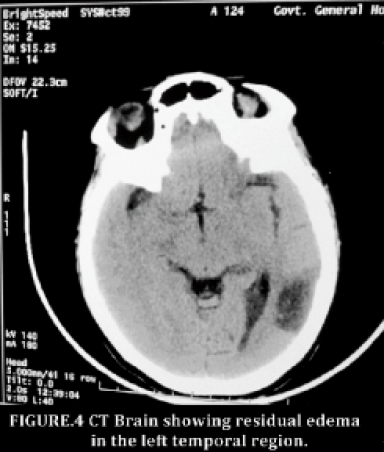

She was treated with intravenous fluids to correct dehydration, intravenous mannitol, acetazolamide tablets, intravenous phenytoin sodium along with bladder, bowel and back care. So further tests were not done. She was treated with low molecular weight heparin initially followed by oral warfarin. Patient was improved gradually and regained full consciousness without any focal neurological cognitive deficits. She was discharged with advice to continue phenytoin sodium orally. Repeat CT scan [Figure: 4] after four months showed residual edema in the left temporal region

- CT Brain showing residual edema in the left temporal region.